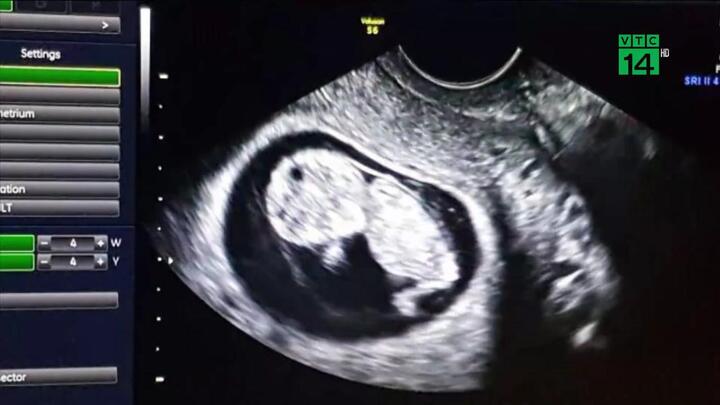

Các bác sĩ Brazil vừa đạt một bước đột phá mới khi giới thiệu em bé đầu tiên trên thế giới ra đời từ tử cung được cấy ghép từ người đã chết.